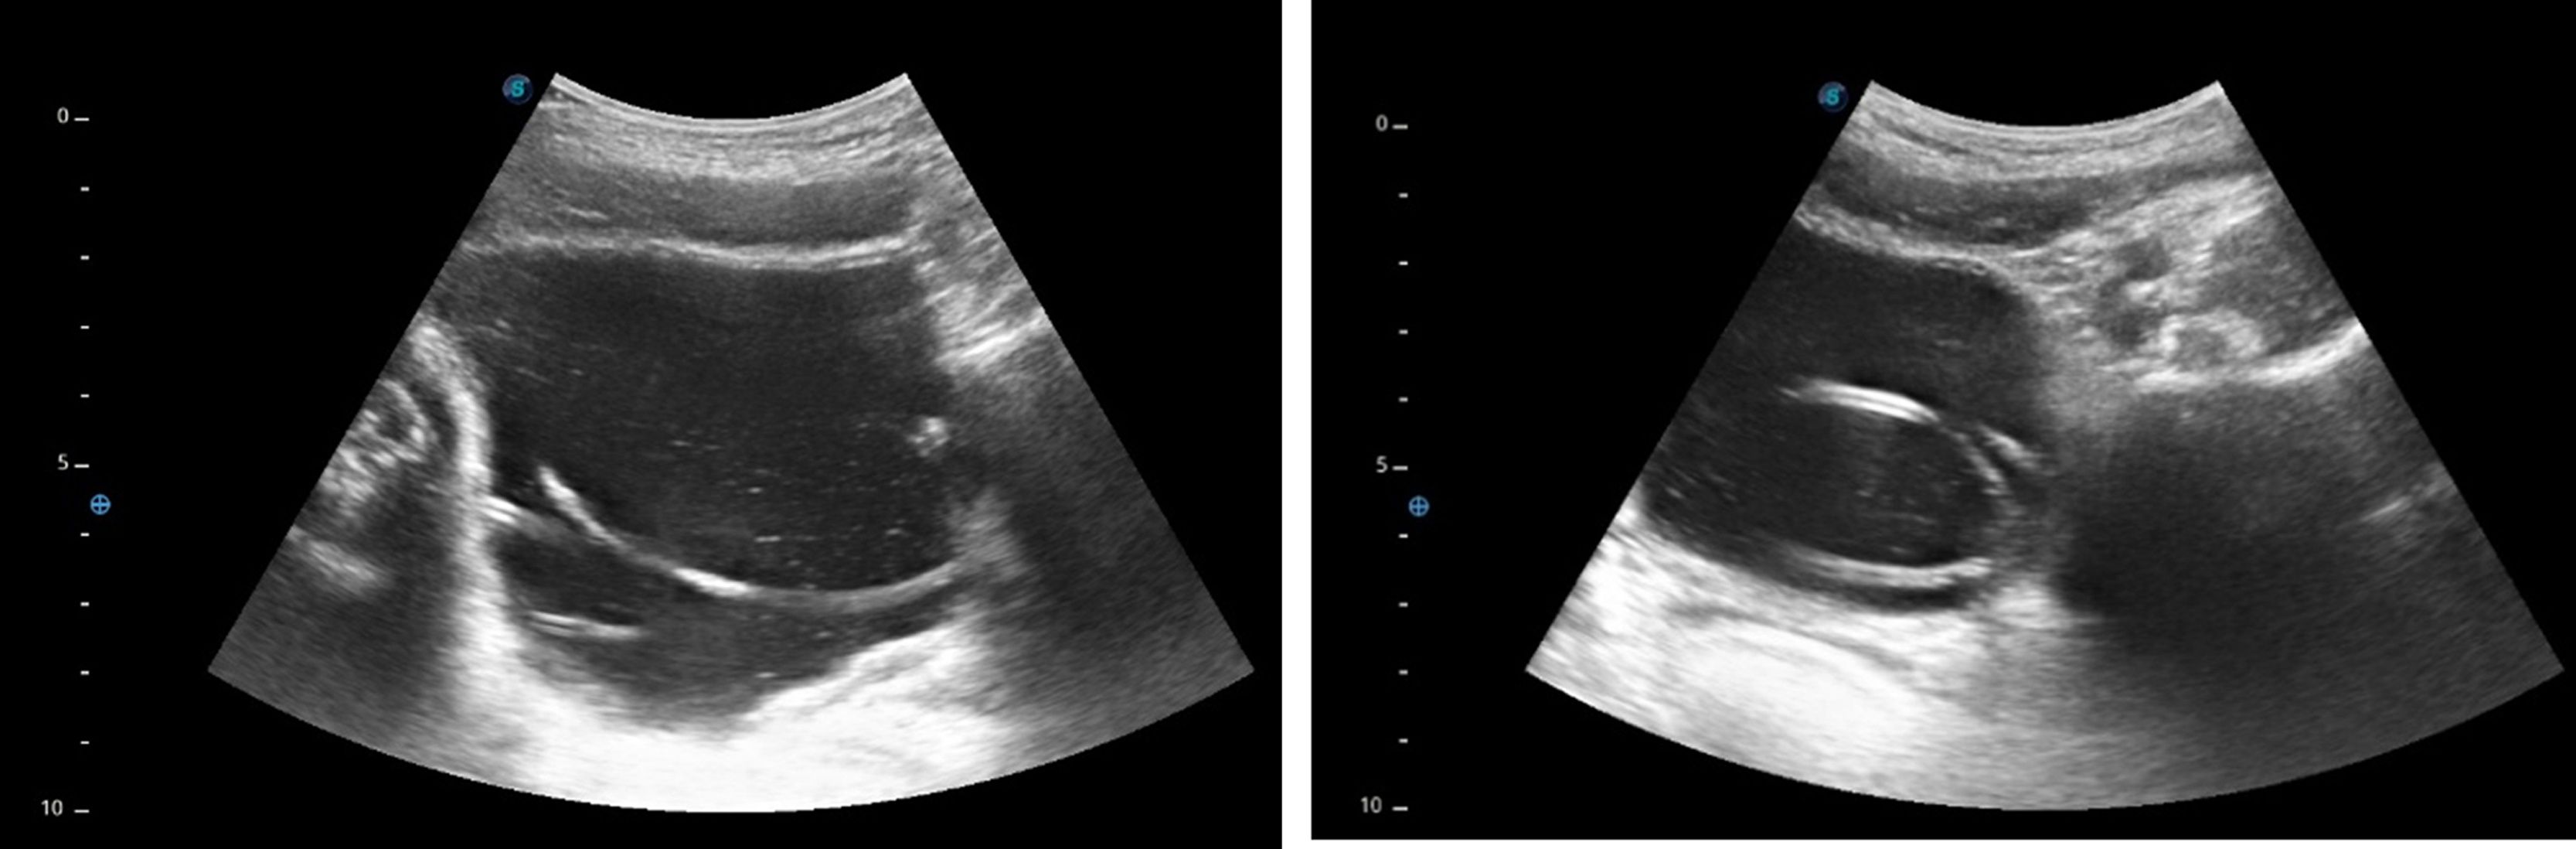

A boy aged 11 years presented to the emergency department with pain in the right testicle and fever of 24 h’ duration. The physical examination evinced scrotal inflammation and erythema with absent cremasteric reflex. The ultrasound examination revealed scrotal wall thickening, increased vascularization and incipient abscesses in the tail of the epididymis, compatible with epididymitis. The patient started antibiotherapy with cefotaxime. Exploratory surgery was performed 24 h later on account of clinical worsening, confirming the presence of severe epididymitis with hydrocele. The urine culture yielded mixed flora. The patient was discharged four days later with a prescription for a 7-day course of amoxicillin-clavulanic acid. An abdominal ultrasound performed on day five to rule out urological disease yielded images suggestive of an intravesical catheter, and the patient was referred to the emergency department. He remained asymptomatic, and he had not previously undergone urinary catheterization. The point-of-care ultrasound confirmed the presence of a looped foreign body (Fig. 1), prompting performance of urgent cystoscopy with removal of a foreign body measuring 75 cm that appeared to be a plastic wire (Fig. 2).